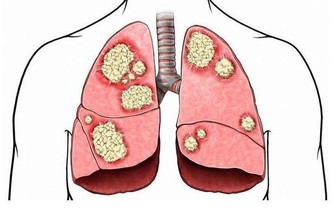

而且寒冷可引起血管收縮,使血流減慢,易誘發心腦血管疾病,